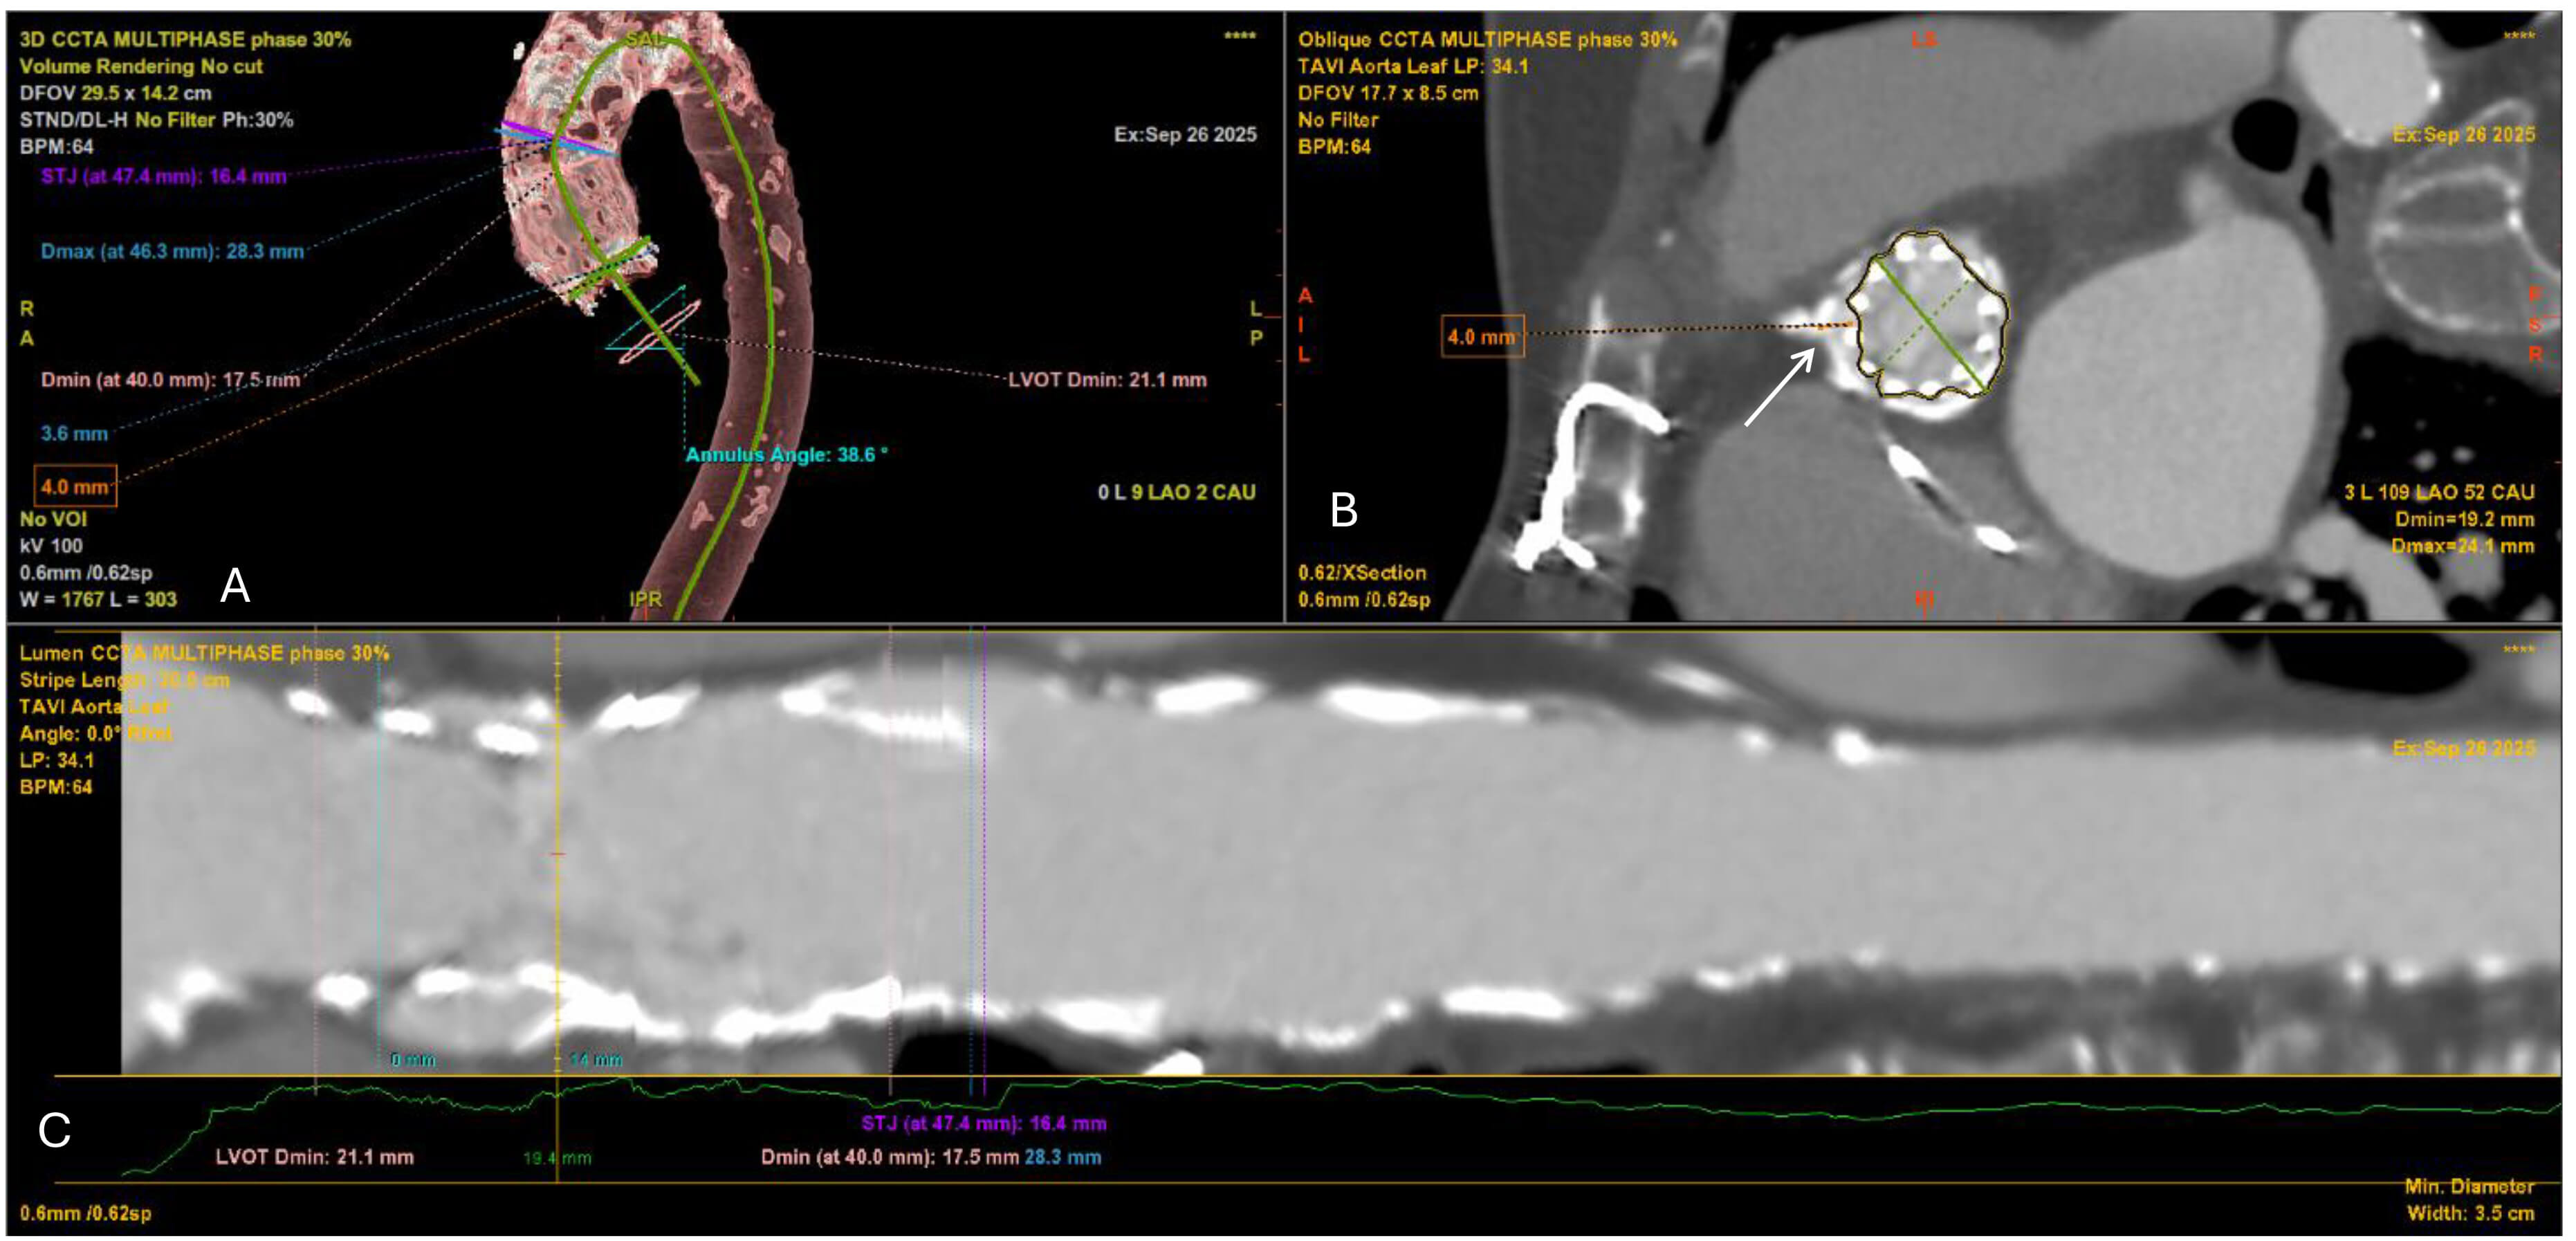

Evaluation of the thoracic and abdominal aorta is equally important. Ulcerated, eccentric, or mobile atheroma in the ascending aorta or arch markedly increases the risk of embolic stroke during catheter manipulation. Detailed visualization of plaque morphology can trigger embolic protection strategies [35, 36]. Furthermore, the management of patients with aortic disease, including abdominal aortic aneurysms (AAA) or previous endovascular aortic repair (EVAR) remains challenging [37]. Other aortic procedures, such as ascending aortic replacement or arch reconstruction, may also influence the feasibility and risk of TAVI. A precise visualisation of the aorta pathology with CT scan, excluding residual dissections, penetrating aortic ulcers or incomplete thrombosis of the false lumen, is crucial to determine the optimal approach for TAVI and to minimize potential complications [38]. Another important characteristic that requires attention is the aortic angulation, which is defined as the angle between the horizontal plane and the aortic annulus plane in a coronal projection [39, 40]. The degree of this angulation can affect the precise positioning of the THV during TAVI making the procedure more challenging (Fig. 2), particularly in an extremely angulated or horizontal aorta (HA) [34]. HAs are often seen in elderly patients, complicating THV passage and should be recognized during planning, particularly for balloon-expandable valves (BEVs) [41]. Finally, the presence of suprarenal atheroma requires consideration because it has been linked to acute kidney injury following TAVI, likely due to increased embolic and contrast load [42, 43]. Thus, systematic characterization of aortic pathology is required to balance access strategy and protection measures.

Fig. 2.

Cardiac CT angiography (CCTA) showing aortic root angulation in the planning of TAVI. Multiplanar reconstruction at 30% of the R–R interval demonstrates an annular angulation of 38.6°, measured between the aortic annulus plane and the horizontal reference line. Accurate assessment of aortic angulation is critical for selecting the optimal fluoroscopic projection and minimizing parallax during valve deployment.

The STJ, forming the outflow boundary of the aortic root, plays a critical role in THV deployment. A narrow or calcified STJ relative to the sinuses may lead to suboptimal hemodynamic performance, while a large, tapered STJ may compromise anchoring and increase long-term the risk of leaflet thrombosis [44, 45]. BEVs are particularly sensitive to STJ constraints, whereas self-expanding valves (SEVs) present better accommodation variability. In BEVs, interaction between the deployment balloon or stent frame and calcification at the STJ can increase the risk of balloon rupture or aortic root injury. Accordingly, assessment of the STJ area and height is essential in all candidates (Fig. 3). A high and spacious STJ relative to the intended valve size is generally favourable for TAVI, whereas a low, narrow, and calcified STJ poses significant technical challenges. In such cases, the use of a shorter-frame THV that can be positioned below the level of calcification may be preferable [45]. Careful CT measurement of the STJ diameter and its relationship to the sinus of Valsalva is therefore essential to guide valve selection.

Fig. 3.

Multidetector CT measurements for TAVI planning. (A) Aortic root assessment at multiple levels, including annulus (diameter at 40 mm), LVOT, sinotubular junction (STJ), and maximum aortic root diameter. (B) Coronary ostium height measurements at 30% cardiac phase, including left and right coronary ostia and sinus height. (C) Sinus of Valsalva dimensions at 30% cardiac phase, showing three sinus diameters relative to the annular plane.

Coronary obstruction, though rare, is a catastrophic complication [46]. CT-derived measurements of sinus of Valsalva width and coronary ostial height can identify patients at increased risk, particularly when cusp length exceeds coronary height [47]. In such patients, preventive measures such as coronary protection, Bioprosthetic or Native Aortic Scallop Intentional Laceration to Prevent Iatrogenic Coronary Artery Obstruction (BASILICA) leaflet laceration, or alternative valve platforms should be considered [48, 49]. Importantly, both coronary arteries must be assessed individually, as asymmetric sinus anatomy may disproportionately endanger one ostium.

Accurate annular sizing is the cornerstone of THV selection (Fig. 4). The aortic annulus, anatomically defined by a virtual ring connecting the basal hinge points of the cusps [50]. The annulus should be measured in systole (20–40% of the R–R interval), when dimensions are largest and most reproducible. CT defines the “virtual annulus” allowing calculation of area, perimeter, and diameters [51]. Area- and perimeter-derived sizing is more reliable than single diameters, particularly in elliptical annuli. Device selection generally involves 5–15% oversizing to minimize PVL while avoiding annular rupture. Therefore, incorrect sizing carries severe consequences as under-sizing contributes to PVL and device migration, whereas oversizing risks annular rupture, especially in heavily calcified rings [52].

Fig. 4.

CCTA with multiplanar reconstruction at 30% of the R–R interval, showing oblique annular plane measurements for TAVI. The mean annular diameter is 24.7 mm, corresponding to an area of 482.5 mm2 and a perimeter of 73.8 mm.